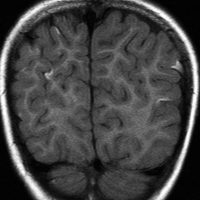

生下時に皮膚の大きな先天性色素細胞母斑があり脳MRIでみられたもの

有毛性母斑があるためにMRIが撮影されました。生後2ヶ月のものです。脳溝に沿うように,灰白質に浸潤するように,散在性の病変がみられます。脳幹部の前面から脳幹内部に浸潤するメラノーシスも特徴的です。